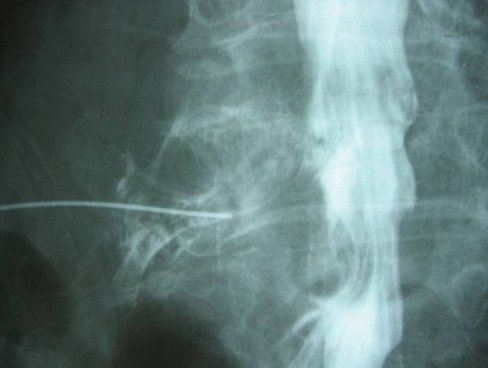

ヘルニコア

腰椎には椎体と椎体の間にクッションの働きをしている椎間板という組織があります。 椎間板は加齢とともにそのクッション性が失われることがあります。椎間板のすぐそばには脊柱管という神経組織が存在する通路があります。椎間板ヘルニアは傷んだ椎間板が脊柱管の方に出っ張ってしまい、神経に当たってしまい炎症を起こし腰痛や下肢痛を起こしてしまう病気です。 腰椎椎間板ヘルニアの治療には飲むお薬、神経根ブロック、手術治療というものが一般的でした。そこに2018年から「ヘルニコア」というコンドリアーゼを有効成分とする腰椎椎間板ヘルニアに対する薬剤が認可されました。椎間板内酵素注入療法という治療方法で呼ばれ、ヘルニコアは椎間板内に注入することにより椎間板の内圧が下がりヘルニアによる神経への圧迫が軽減することにより症状を改善させることが期待されます。 局所麻酔で行います。X線透視で部位を確認しながらヘルニアを生じている椎間板に細い針を刺し、ヘルニコアを注入します。治療に要する時間は約5分程度です。当院では1泊2日で行っております。 椎間板内酵素注入療法(ヘルニコア)はすべての腰椎椎間板ヘルニアに対して適用されるわけではありません。また、人生で一度きりの方法になります。外来で担当医師にご相談ください。